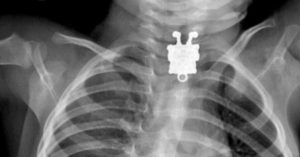

- Любые батарейки (хоть пальчиковые, хоть мини, хоть так называемые таблетки).

При возникновении подозрений в том, что ребенок проглотил лезвие, батарейку, иголку или иной опасный предмет, необходимо незамедлительно обратиться к детскому хирургу. До осмотра важно, чтобы малыш пребывал в покое, не бегал. Категорически запрещается делать клизму, вызывать рвоту, давать слабительное и прочими способами помогать инородному предмету выйти из тела.

«Самое страшное – это когда ребенок глотает батарейку, острые предметы или стекло, – говорит врач. — В первом случае это грозит химическим ожогом слизистой, во втором ее повреждениями и воспалением. — Монетки, магнитики, разные металлические предметы тоже требуют наблюдения.